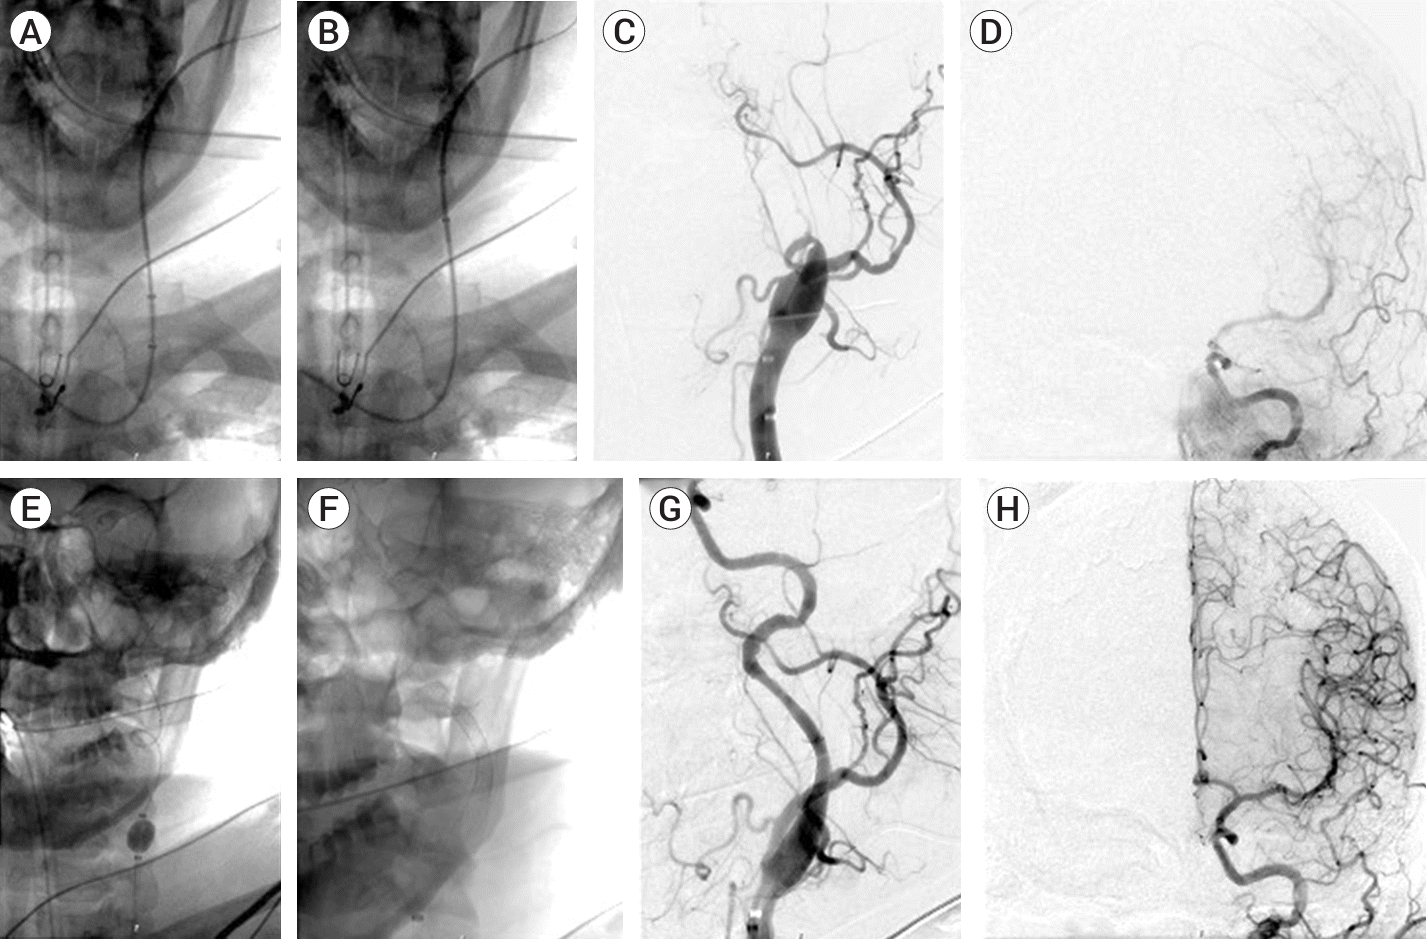

Patient #7 (Fig. 2) presented with acutely symptomatic left ICA dissection that resulted in left cerebral hemisphere hypoperfusion. While the initial admission NIHSS was 3, the patient subsequently worsened to an NIHSS of 8 with severe aphasia and right arm plegia. The right radial artery was accessed as described above, and a cervical angiogram demonstrated left ICA dissection with an intramural thrombus resulting in occlusion of the left ICA. Again, the balloon was inflated prior to crossing the stenosis. No DEP could be used due to the location of the dissection extending into the horizontal petrous ICA segment. No intracranial large vessel occlusion was seen after the dissection site had been crossed with a microcatheter and microwire. The inflated balloon also provided additional support for subsequent stent reconstruction with a Surpass evolve 4×30 mm, Surpass evolve 4×25 mm, Onyx Frontier 4×22 mm Drug-eluting stent, and Acculink 6-8×30 mm carotid stent. Post stent angiogram demonstrated successful reconstruction of the left ICA with a widely patent stent construct spanning the entire length of the cervical ICA to the horizontal petrous segment, and no evidence of distal thrombo-embolic complication. The patient made an excellent recovery with a discharge NIHSS of 0 and a 90-day follow-up mRS of 0.

Fig. 2.

Patient #7 with acutely symptomatic left internal carotid dissection. (A-B) Walrus catheter tracking within the left common carotid artery over the diagnostic catheter and wire. (C) Left common carotid angiogram demonstrates left ICA dissection with intramural thrombus resulting in occlusion of the left Internal Carotid Artery (ICA). (D) Pretreatment angiogram of left ICA circulation demonstrates no intracranial large vessel occlusion. (E) Walrus catheter inflation to increase the stability of the balloon guide catheter for stent delivery and deployment. (F) Native view of stent construct. (G, H) Post treatment left common carotid angiogram demonstrates widely patent stent construct with reconstitution of left ICA, no significant residual stenosis, and brisk intracranial flow without distal thromboembolic complication.